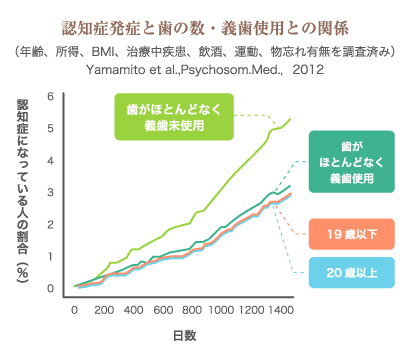

食べ物を歯でしっかりと噛むことは、脳に刺激を与えるため、認知症の予防に効果的です。しっかり噛むためには「歯」が必要ですが、歯が抜けてしまったという方もあきらめることはありません。

実際、天然の歯がほとんど無くても、義歯を使用してしっかり噛むことができていれば、認知症になりにくいという調査結果も出ています。